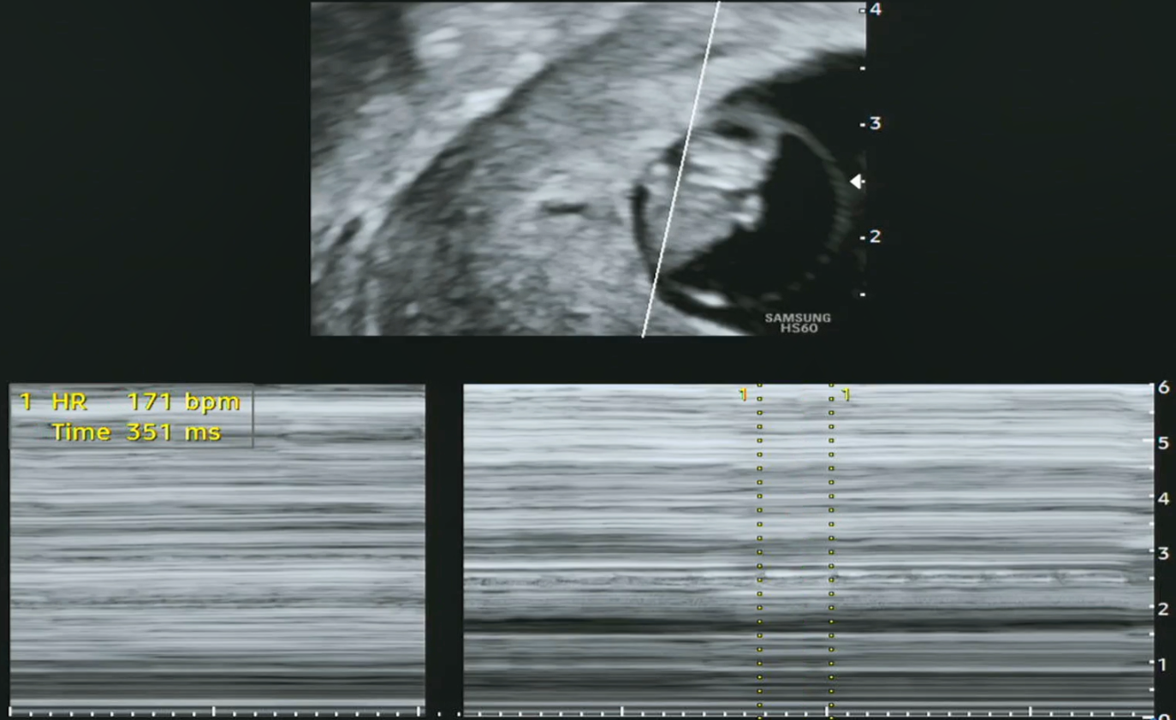

임신 8주 차 아기의 크기가 1.5~1.6cm 정도로 성장한다고 하는데, 우리 '팡팡이'는 1.67cm라 딱 주수에 맞게 크고 있다고 하네요. 그리고 심장박동수도 점차 증가하여 9주까지는 160~180 bpm 정도라고 하는데, 현재 171 bpm이니 정상이라고 합니다(인터넷에서 검색해 보니 조금씩 다르게 수치가 나오기는 하더라고요).

[왼쪽-태아 심장박동수(171 bpm), 오른쪽-태아 크기(1.67 cm)]